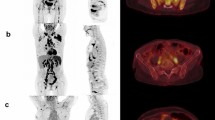

The vertebral bodies T10–L5 were manually segmented using three-dimensional volumes of interest (VOIs) on axial, sagittal, and coronal reconstructed bone marrow CT images. Areas next to the cortical bone, larger bone marrow vessels (e.g., the basivertebral vein and its bony canal) as well as focal lytic lesions, and areas of bony sclerosis were carefully excluded (Fig. 1). Focal lesions which had to be excluded from segmentation are summarized in Table 1. The segmentations were performed by three readers in consensus in a blinded fashion. Two of the readers were radiologists with 30 years and 4 years of experience in diagnostic imaging. For assessment of reliability, segmentations were additionally performed by two readers independently following feature extraction.

Unenhanced DECT for post-processing and generation of non-calcium “bone marrow image data” which were used for manual segmentation of the vertebral bodies T10–L5. Areas next to the cortical bone, larger bone marrow vessels (e.g., the basivertebral vein and its canal), and focal lytic lesions were excluded